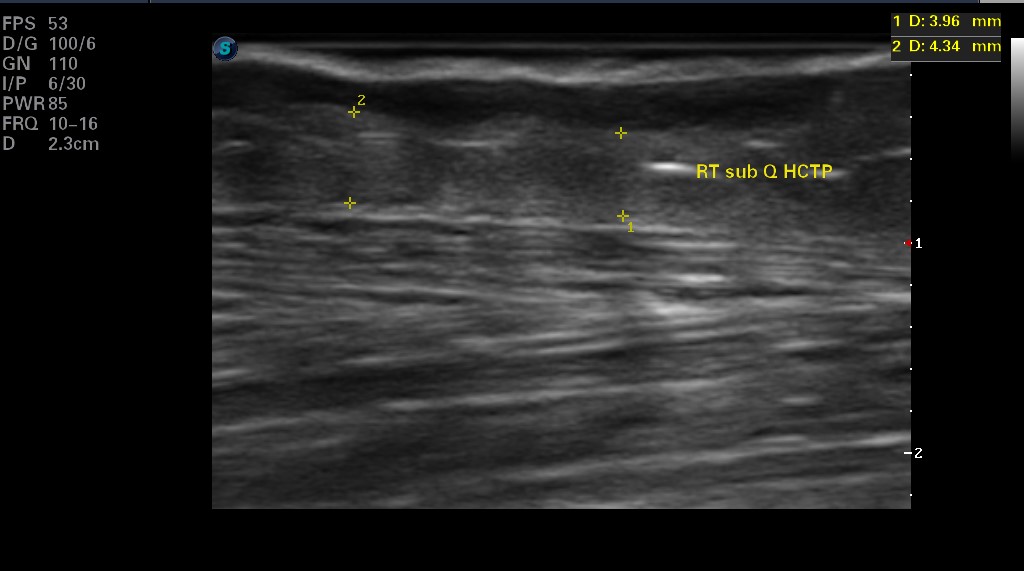

Sixteen months after initiating DECM therapy, the team performed ultrasound evaluation of the subcutaneous tissue for appearance and thickness of the fat, and the difference between the CTP and DECM healing was profound. On the right limb, the wound healed with a CTP occurred over the anterior compartment of the leg (just lateral to the tibial crest) and had remained healed for more than 5 years. The measurement of the subcutaneous tissue was 3.96–4.34mm thick (Figure 3). The physical appearance of that site was concave, atrophied, and with telangiectasia (Figure 4). The same limb healed with a DECM over the posterior compartment (just medial to the tibial crest) measured subcutaneous thickness of 14.97–15.12mm (Figure 5). The physical appearance was not concave, and the skin did not demonstrate telangiectasia, atrophy, or discoloration (Figure 6).